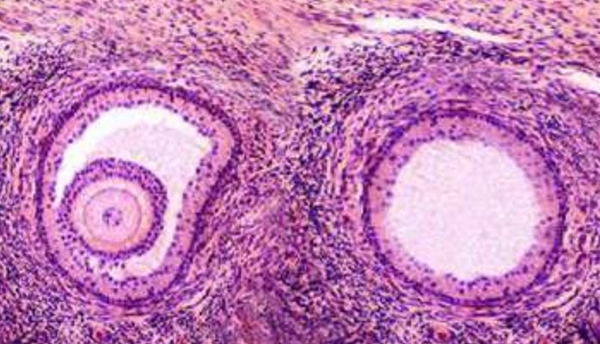

卵泡只有发育成熟才能诱发排卵,此时排出的卵子才会成熟健康且功能健全。而卵泡成熟的特征是呈圆形或椭圆形、直径达18-25mm、卵泡内呈无回声区、清亮纯净、边界清晰。若女性因卵巢疾病,如多囊卵巢综合症、下丘脑-垂体-卵巢轴功能异常或是内分泌紊乱等,导致卵泡发育不良,就会造成取卵数量降低,与前期看到的基础卵泡数量不同。